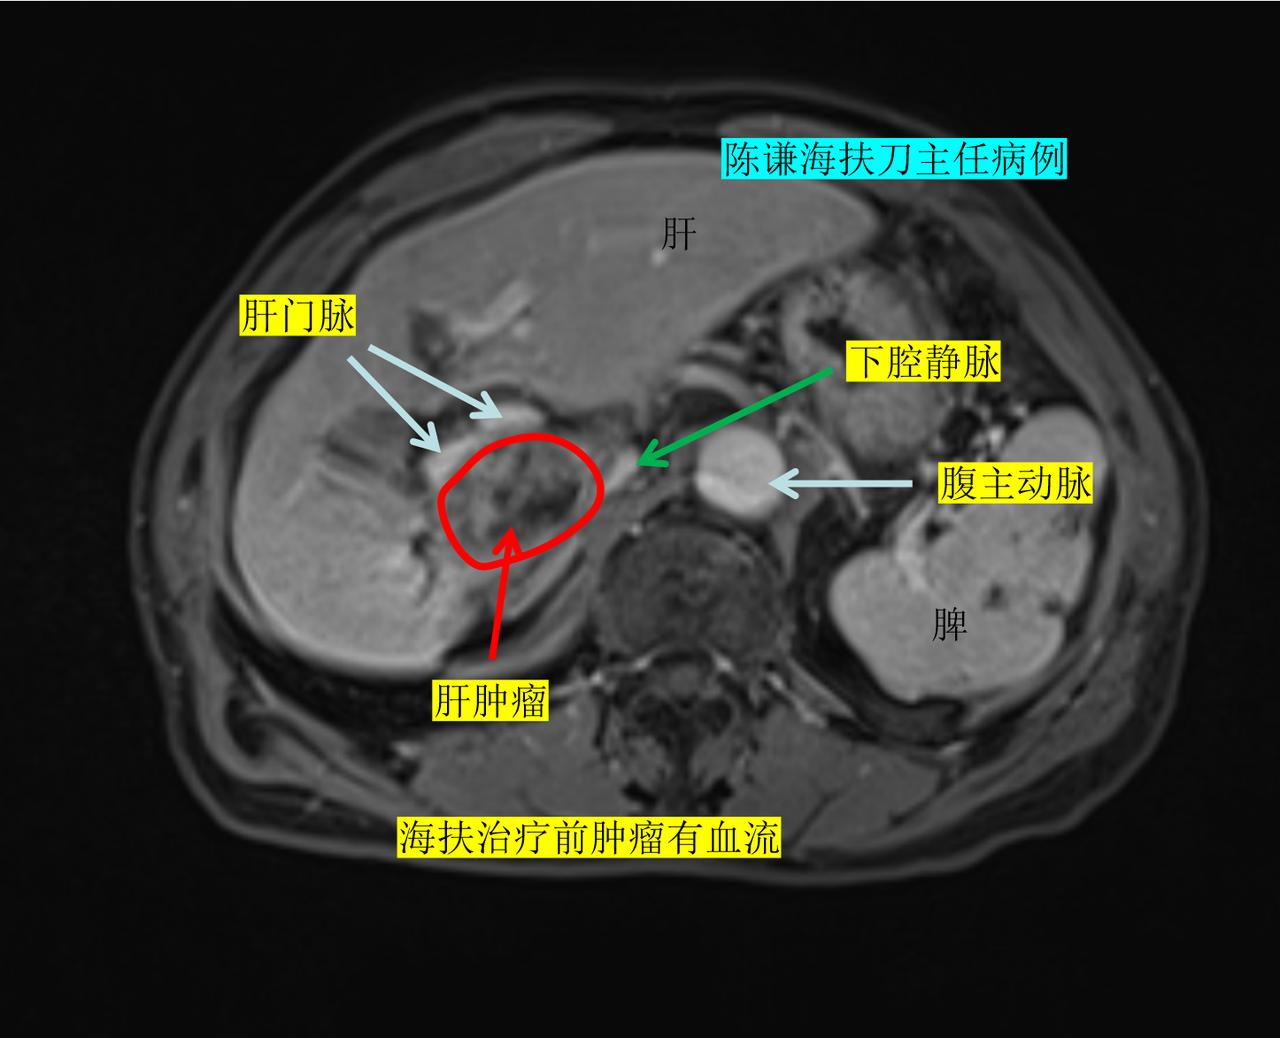

这是我们上周才治疗的一名晚期肝癌患者,病人74岁,来自江西,患者确诊原发性肝癌后,在当地做了介入治疗,射频消融治疗等综合治疗后,肿瘤有残留复发。 现在复查增强磁共振显示肿瘤紧邻门静脉、下腔静脉,旁边是胆囊,靠近头侧是肝静脉,病灶位置想到特殊,常规的消融治疗手段风险很高,很容易损伤血管,并且也有损伤胆囊和肠道的危险。在了解到海扶刀对靠近血管的肿瘤进行安全消融之后,不远千里从江西至我们中心进行消融治疗。 患者术中效果消融满意,术后复查增强磁共振,显示肿瘤100%消融,肝静脉,门静脉下腔静脉都没有损伤,患者术后第二天就正常出院了。 海扶刀治疗是利用超声波聚焦后直接烫伤肿瘤,具有创伤小,效果确切,术后恢复快,无放射性风险等优势,对疑难特殊部位的肝肿瘤具有独特优势。肝癌 海扶刀